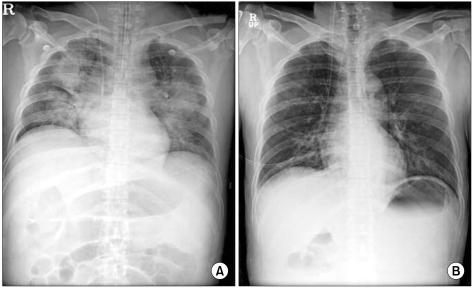

Opioid analgesia is the primary pharmacologic intervention for managing pain. However, opioids can cause various adverse effects including pruritus, nausea, constipation, and sedation. Respiratory depression is the most fatal side effect. Therefore, cautious monitoring of respiratory status must be done after opioid administration. Here, we report a patient who suffered from respiratory depression with deep sedation and aspiration pneumonitis after intrathecal morphine administration.

阿片类镇痛药是治疗疼痛的主要药物干预手段。然而,阿片类药物会引起各种不良反应,包括瘙痒、恶心、便秘和镇静。呼吸抑制是最致命的副作用。因此,阿片类药物给药后必须谨慎监测呼吸状态。在此,我们报告了一例患者在鞘内注射吗啡后出现呼吸抑制伴深度镇静和吸入性肺炎。